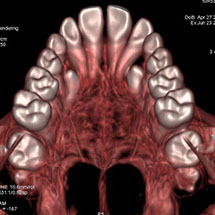

Scanner dentaire

Le scanner dentaire permet entre autres d'explorer des anomalies liées au développement des dents, de repérer les foyers d'infection ou des kystes autour des racines dentaires. Il permet également de préparer un implant métallique en vue de remplacer une dent manquante.

Le scanner dentaire se fait à l'aide d'un appareil équipé d'un tube à rayon X. Lors du déroulement de l’examen, le tube du scanner est en rotation autour du patient qui est placé sur un lit mobile. L'appareil permet alors de réaliser une imagerie en "coupes", utile à l'exploration des dents et des arcades dentaires. Grâce à un traitement informatique et à ces clichés, il est possible de reconstruire des images en 2D ou 3D (modélisation dans l’espace).

• Bilan avant pose d’implants dentaires, pour repérer les zones de passage des nerfs et mesurer l’épaisseur de l’os afin de calculer les dimensions optimums de l’implant.